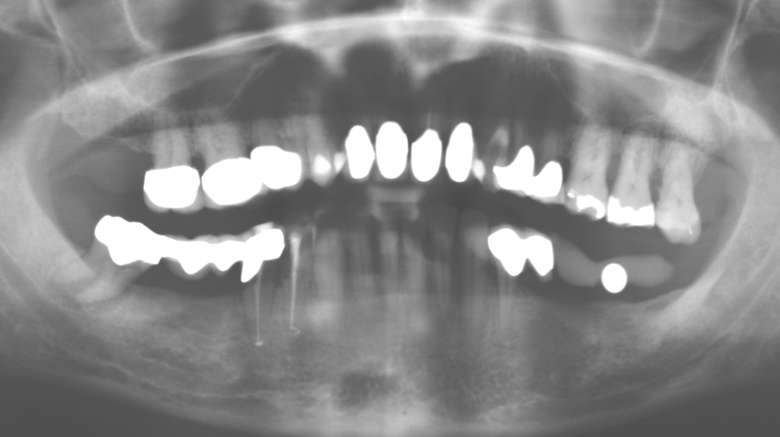

A 52-year-old patient presented in our clinic for the first time in 2004 following tooth loss in the third quadrant, expressing a desire for a new prosthetic restoration. Periodontal and radiological diagnostics revealed the need for extensive periodontological treatment. In addition, teeth 48, 28 and 27 were attributed a very poor prognosis and were subsequently extracted (Fig. 1). Following the successfully completed, systematic periodontological treatment, a fixed dental implant was inserted with the introduction of five implants in tooth regions 35, 36, 37, 46 and 47. Prosthetic treatment of the natural teeth was effected with veneered zirconium dioxide ceramic crowns; the implants were composed of two-piece, individual zirconium dioxide abutments and similarly veneered crowns made of a zirconium dioxide ceramic (Cercon base colored, Dentsply Sirona Lab). Definitive insertion of the prosthetic restoration occurred in 2005.

The ten-year check-up revealed no indications of advancing clinical attachment loss or peri-implant bone substance loss (Fig. 3).